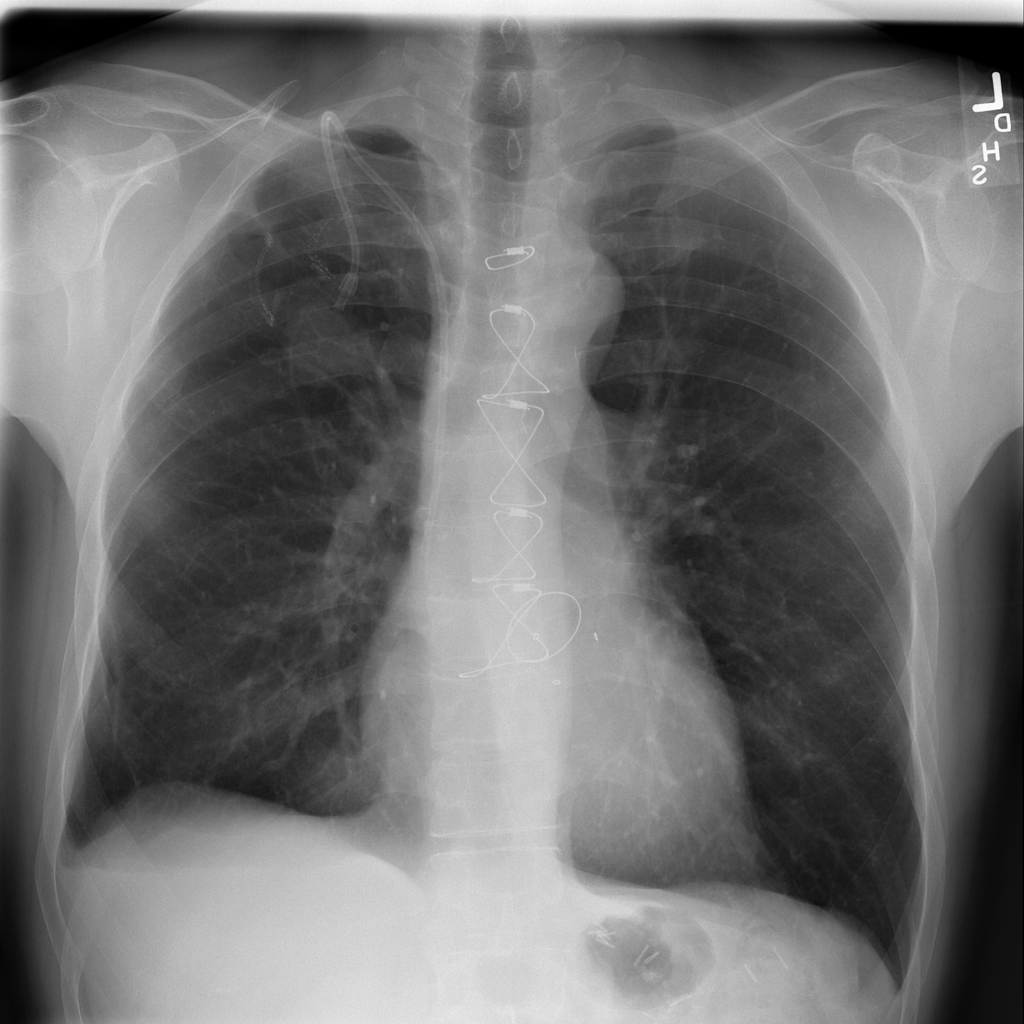

PAT-C255 · IMG-000Emphysema

PAT-C255 · IMG-000

PA